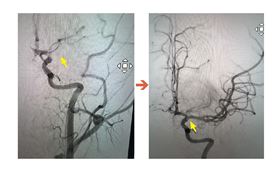

搶救腦中風爭分奪秒 引入動脈取栓術

缺血性腦中風佔中風7成 晚1分鐘搶救腦細胞死亡上百萬...